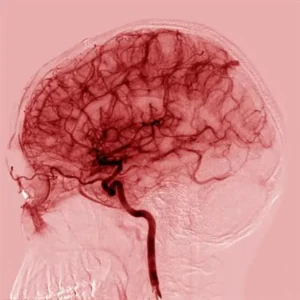

qEEG Brain Mapping in Denver

A non-invasive assessment that creates a visual map of your brain’s patterns—attention, arousal, and regulation. It provides an objective baseline to track change over time and choose the right starting point, so your treatment plan is informed by data, not guesswork. Safe, medication-neutral, and designed to inform—not label.